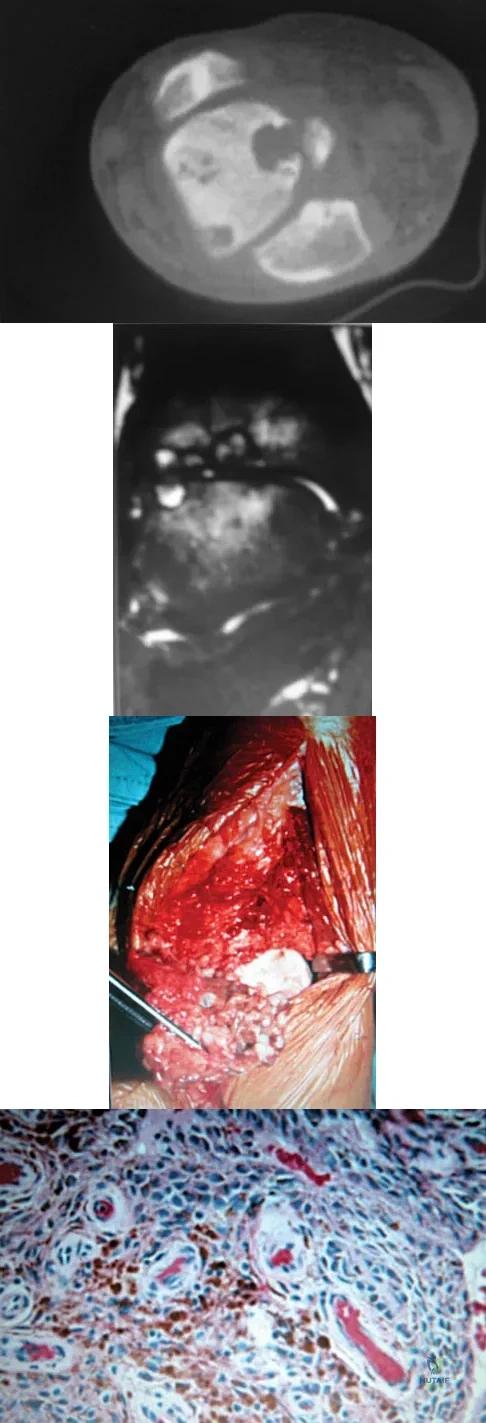

A 30-year-old man has had intermittent swelling of his right ankle for the past 6 months. He denies any history of trauma. Radiographs reveal osteolytic changes on both sides of the joint. An axial CT scan and a T2-weighted MRI scan are shown in Figures 40a and 40b. He undergoes surgical excision. An intraoperative photograph and a biopsy specimen are shown in Figures 40c and 40d. What is the most likely diagnosis?

Explanation